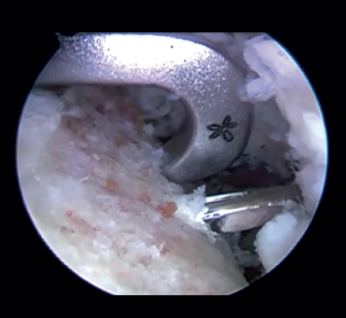

Introduction and fixation of the graft (Figure 4)

The cannula is removed from the anterior portal, from the posterior viewing portal, rotator interval is widened in order to facilitate introduction of the graft. Using both monofilaments, the graft traction threads are inserted from front to back. The graft is introduced into the joint, applying traction upon the threads from the posterior position. The graft is placed in line with the defect and within the capsulolabral structures. Once the graft is positioned in its final anterior position, the posterior buttons are placed by means of the traction threads and are fixed via a self-stabilizing running suture, tightening to 100 N with the help of a tensiometre, in sequence.

Figure 4. View from the posterior portal (left shoulder). Insertion of the graft by means of the traction threads and positioning in line with the bone defect.